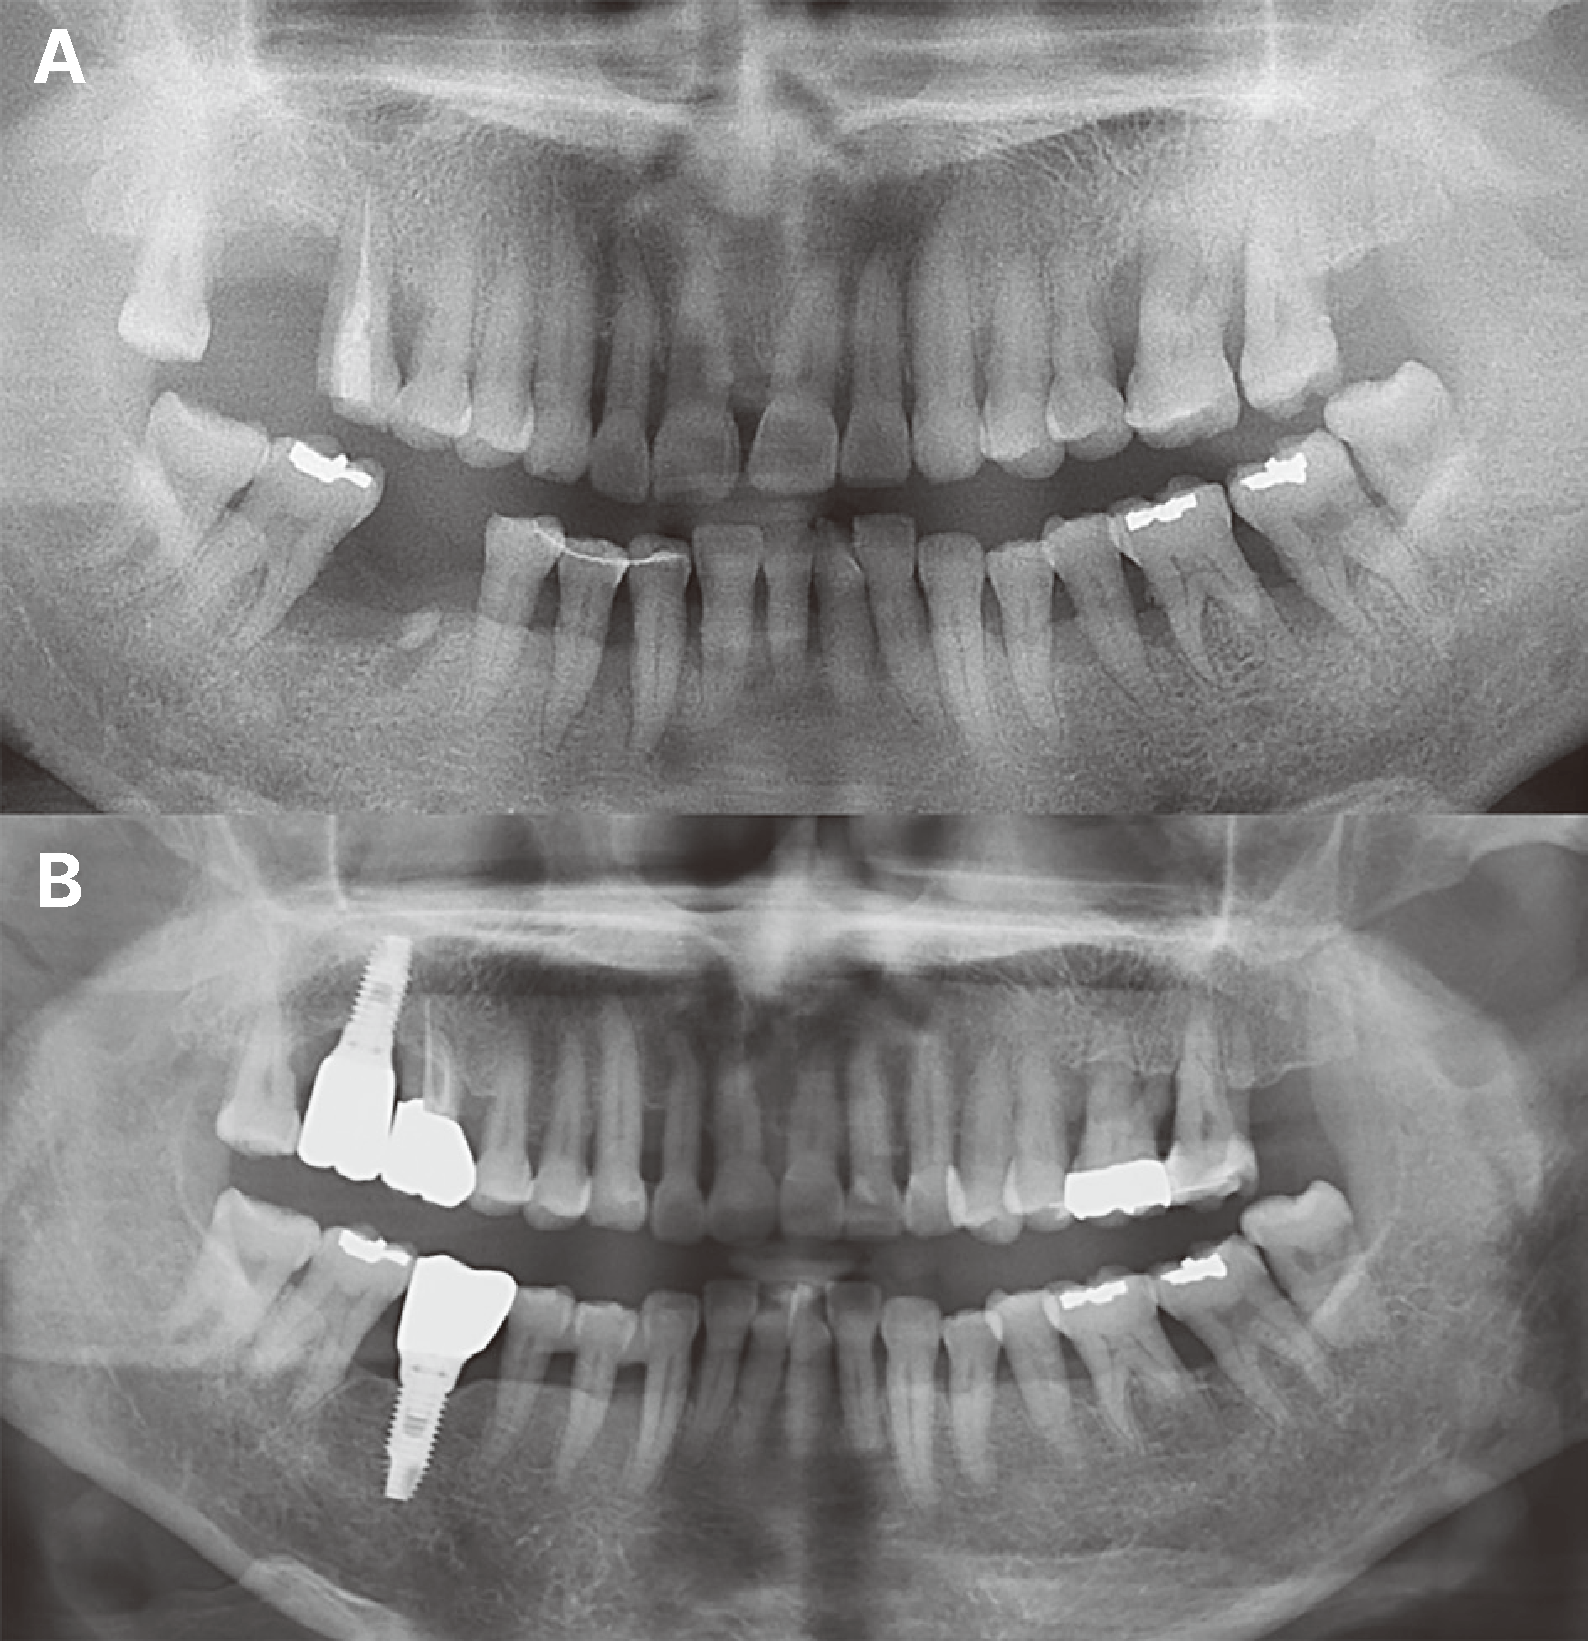

Fig. 2

Preoperative periapical radiograph: note that the distance from the contact point to the alveolar bone crest is within 5 mm (A). Panoramic radiograph taken 9 years after periodic curettage: The crestal bone level has been well maintained over the 9- year period (B).